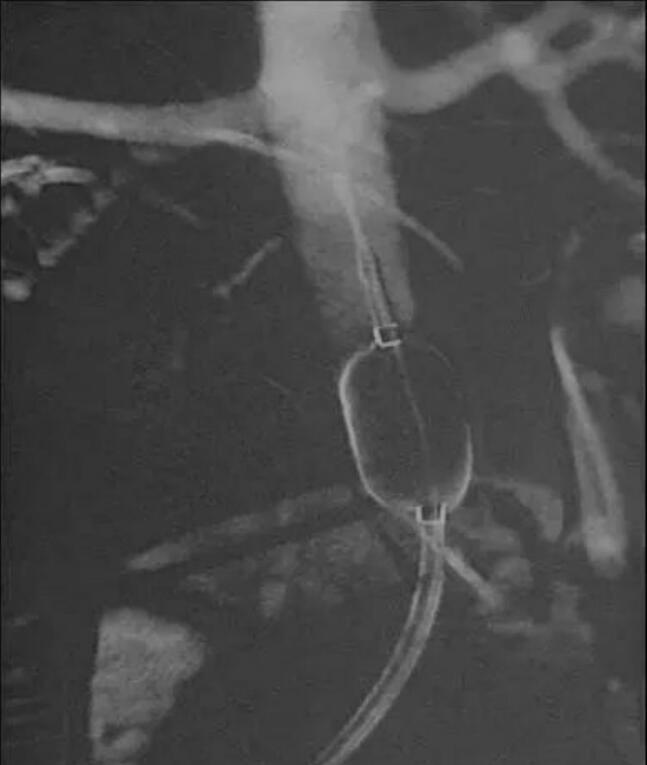

梧州市工人医院产科日前联合介入室、超声科、麻醉科完成了2例腹主动脉球囊阻断下辅助凶险性前置胎盘剖宫产术,取得良好的效果。介入室医师根据术前MRI图像选定合适球囊直径,在超声监视下于剖宫产术前将球囊导管引入腹主动脉内肾动脉开口与腹主动脉分叉之间,固定导管鞘和球囊导管。之后在联合麻醉下行剖宫产术,选择尽量避开前置胎盘的子宫切口切开子宫,娩出胎儿的同时立即充盈球囊阻断腹主动脉,用药物促进宫缩,徒手剥离胎盘并尽量清除植入肌层的胎盘组织,采用可吸收线局部缝扎、折叠缝合、CHO四边形缝合和B-Lynch缝合以控制产后出血。腹主动脉球囊阻断后,术中出血量和输血量明显减少,术野清晰,利于手术操作和精准止血,保住了患者子宫。

在腹主动脉下段预置球囊的全程都是在超声监视下进行,球囊送到位置后进行预扩张,用超声监测到双肾动脉血流通畅,而腹主动脉下段无血流回声,确定球囊放置到位,即固定球囊导管,尽量避免辐射,保证了胎儿安全。该技术在广西区内处于领先水平。